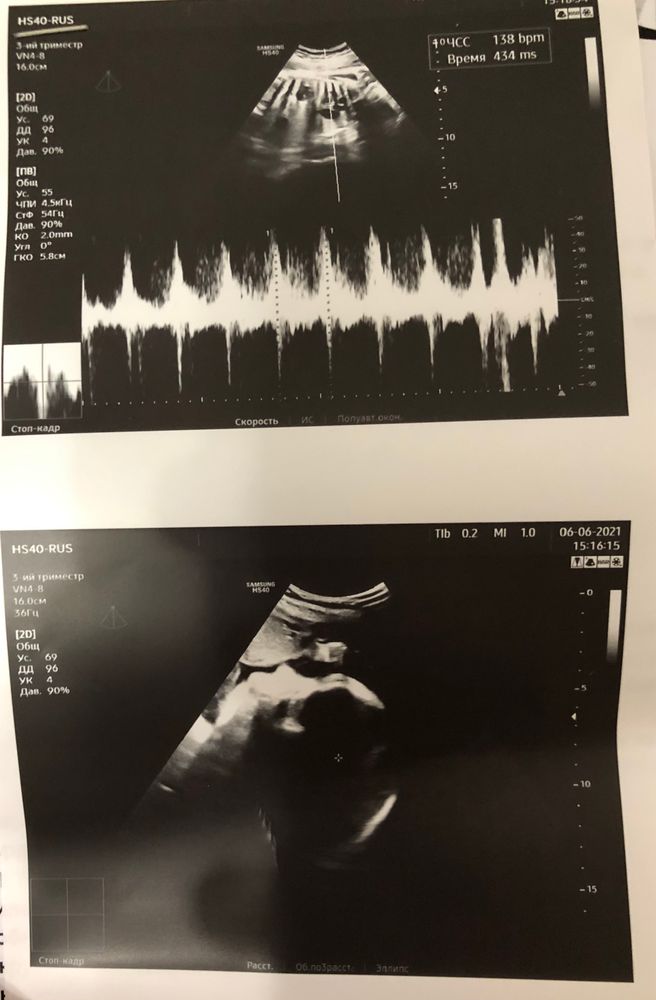

Третий скрининг и наше первое КТГ🌸

УЗИ, КТГ, доплерпочему-то в этот скрининг переживала меньше всего:) все в норме, наша малышка соответствует сроку.

1700 гр и 40 см💕